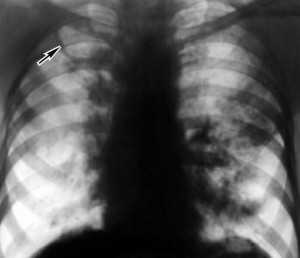

Эта форма туберкулеза наблюдается у больных крайне редко. Но в случае заболевания течение болезни происходит в острой форме. Симптомами болезни выступают фебрильная лихорадка, интоксикация, одышка и сухой кашель. Пробы на туберкулез довольно часто могут быть отрицательными, однако на рентгене все легкие покрыты небольшими тенями.

Диссеминированное туберкулезное заболевание легких. Заболевание появляется как последствие широкого гематогенного расширения туберкулезной инфекции. Началом недуга, в основном, есть лихорадка фебрильная, после неё быстро проявляется интоксикация. Человек страдает наличием сухого кашля и одышки. Анализ туберкулеза в легких осуществляется способом рентгенографии. Одновременно, анализ мокроты не дает результатов по причине отсутствия в ней микобактерий. Ещё о диагнозе свидетельствует биопсия трансбронхиальная. Осложнениями такого состояния способны стать сердечно-легочный недостаток, анемия, отсевы гематогенные в различные органы и пр.